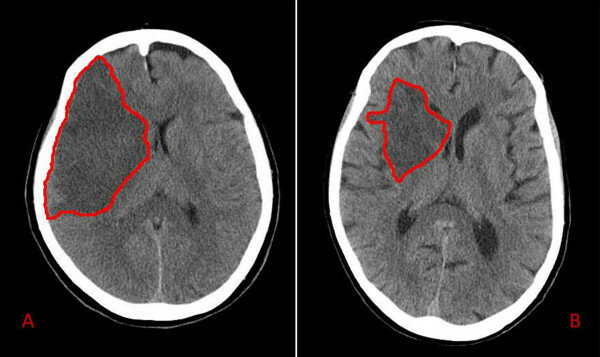

• Diagnosticar un Ataque cerebrovascular

Diagnosticar un Ataque cerebrovascular

En los años setentas se uso la tomografia computarizada para diagnositcar un Ataque cerebrovascular y saber si era un problema hemorragico o circulatorio